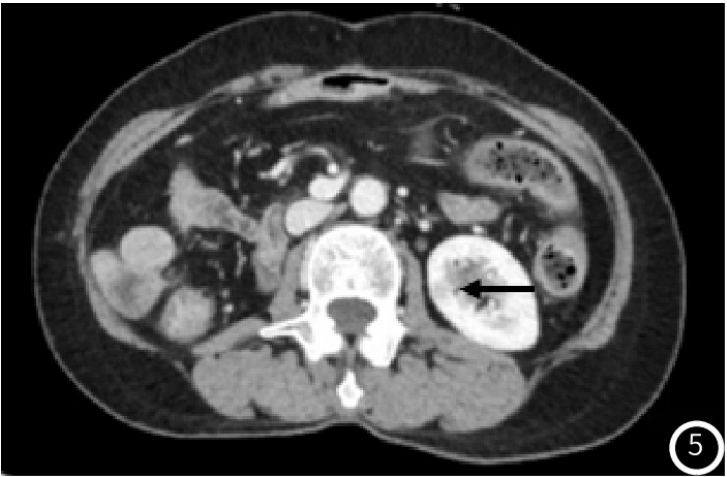

示胰头类圆形低密度结节,大小约14mm×12mm,增强扫描动脉期结节明显均匀强化(图1),强化程度高于正常胰腺实质,静脉期强化减低,边界清;术后4年常规胸腹部CT

图5 CT增强髓质期左肾结节强化减低(黑箭头);